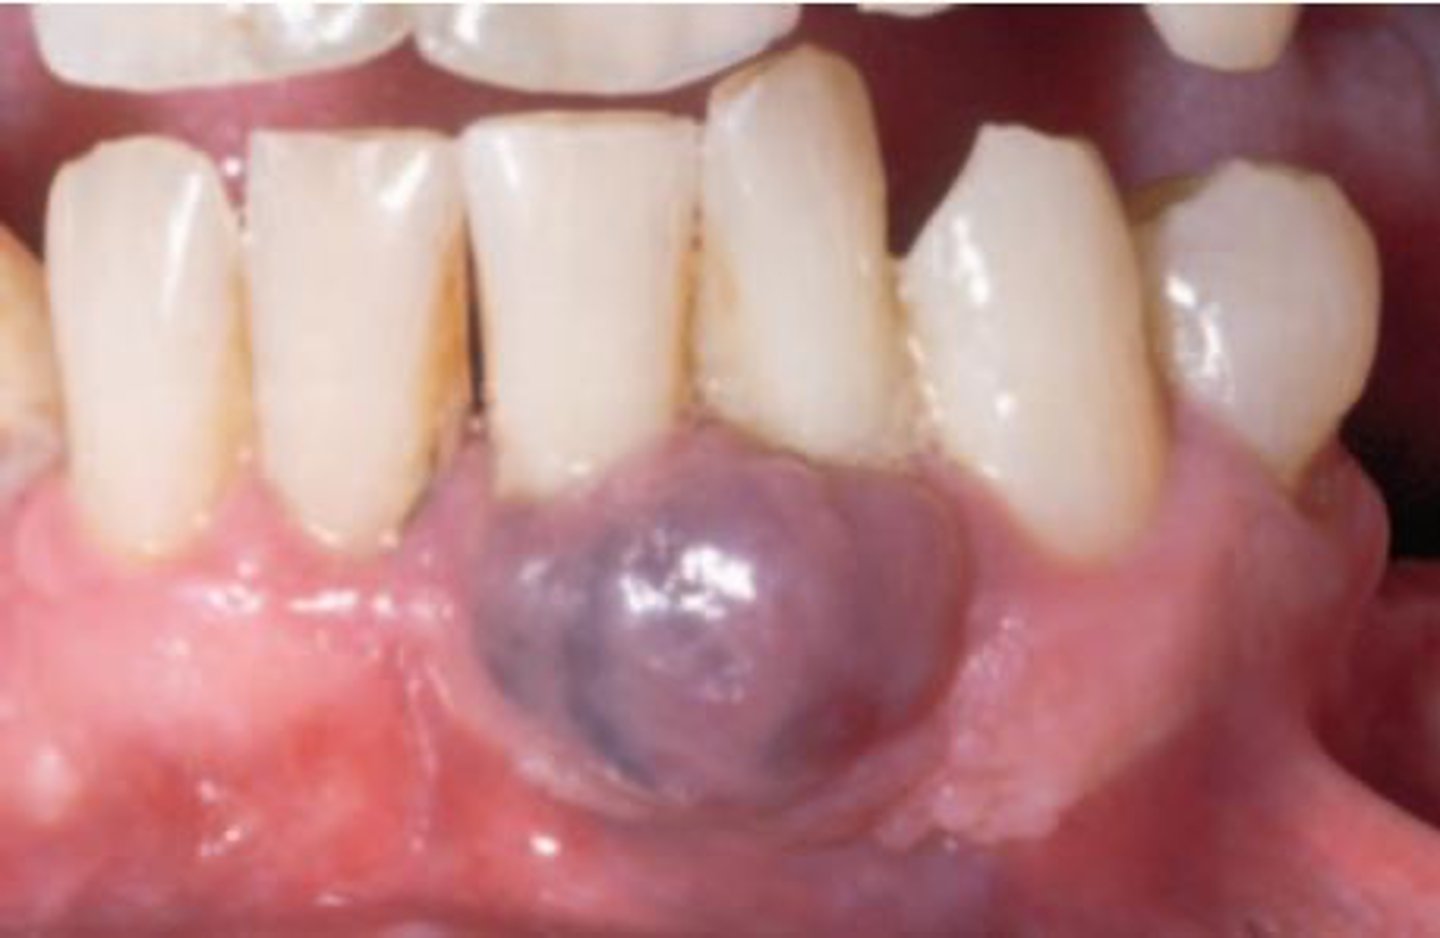

What is a painless, benign, dome-shaped, soft fluctuant nodule with a soft blue hue and some what translucent?

mucocele

Which location is MOST commonly associated with a mucocele?

lower lip

The most common cause of mucocele is:

trauma to minor salivary gland duct